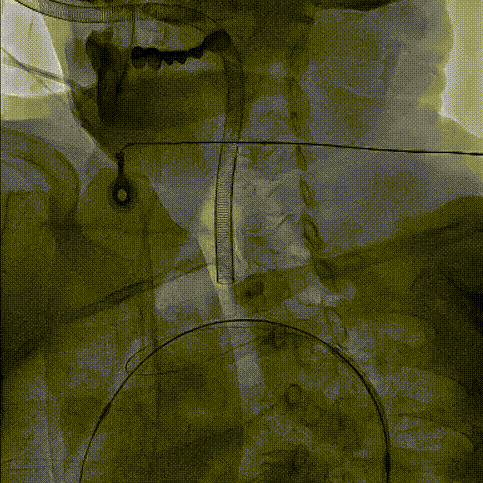

TriGUARD3™抗栓塞远端脑保护装置在介入瓣膜释放后撤出,术中未出现任何并发症。

TriGUARD3™撤出

TriGUARD3™作为在TAVR手术过程中第一个进入人体,最后一个撤出的器械,从植入,球囊预扩,瓣膜输送系统过弓跨瓣,瓣膜释放,输送系统撤出,直至TriGUARD3™脑保护装置撤出,全程保护大脑血管,对降低患者新发脑损伤,减少相关并发症的发生起到良好的效果。

术后脑保护装置留存的斑块